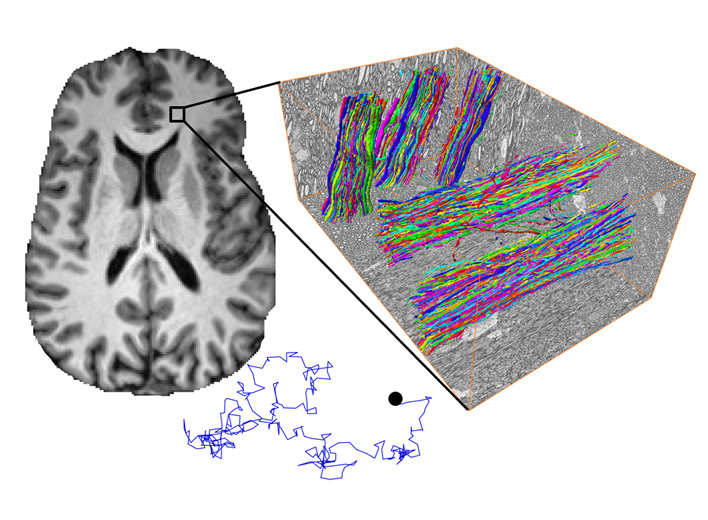

This project develops and validates biophysical models of diffusion and nuclear magnetic resonance relaxation to quantify tissue microstructure in the brain—such as axonal integrity, inflammation, fiber orientation dispersion, axonal diameters, axonal beading, undulations, and water exchange—using diffusion methods and a leading-edge Siemens Connectom.X gradient system.